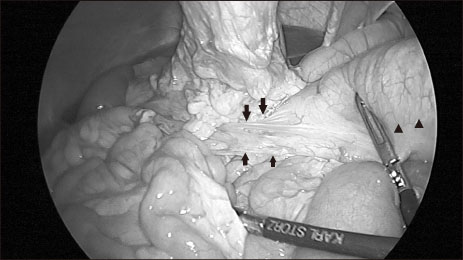

During laparoscopic exploration, adhesion of the transverse colon to the stomach wall of the gastrostomy site was seen and appeared twisted (

Fig. 3). Proximal transverse colon was redundant and upstream dilatation from the twisted transverse colon to the ascending colon and the cecum was found with reversed intestinal anatomy, as identified on preoperative images. Sigmoid colon was collapsed and not redundant, so the suspicious sites of endoscopy were not related to the symptoms. Adhesiolysis and fibrous band lysis between the transverse colon and adherent soft tissue was done. Redundant proximal transverse colon was resected via mini-laparotomy site, and end-to-end colocolic anastomosis was performed (

Fig. 3Adhesion of transverse colon on stomach wall and twisting (arrow) with upstream colon dilatation (arrowhead).